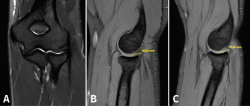

Estos autores proponen un sistema de gradación según los hallazgos en la RM, tanto del grado de tendinosis como del grado de retracción del tendón desinsertado del epicóndilo (Figura 9):

Figura 9. Imágenes de resonancia magnética que ilustran los grados de afectación tisular de la clasificación de Walton. Se pueden apreciar cortes coronales y axiales de tendinopatía del espesor del tendón sin rotura (A) y de los distintos grados de lesión con rotura de la inserción según su longitud de separación del epicóndilo; B: grado 1 (< 2 mm); C: grado 2 (2 a 5 mm); D: grado 3 (> 6 mm).

Según el grado de tendinosis:

- Grado 1. Normal-leve: baja intensidad de señal homogénea o pequeños focos de aumento de señal en el estudio de supresión grasa en T2.

- Grado 2. Moderada: aumento de señal moderado en T2.

- Grado 3. Severa: aumento de señal generalizado en el tendón en T2.

Según la longitud de separación de la rotura respecto al epicóndilo:

- Grado 1: 0-2 mm.

- Grado 2: 2-5 mm.

- Grado 3: > 6 mm.